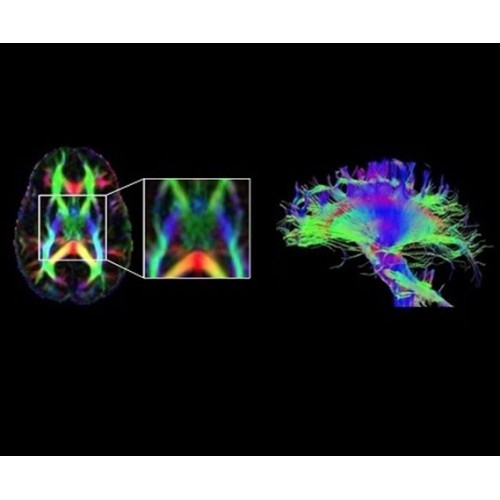

В системе SIGNA PET/MR есть все инструменты, необходимые для выявления маркеров разных заболеваний и для создания новых протоколов. ПЭТ/МРТ можно использовать совместно с мультиядерной спектроскопией в лаборатории in vivo для изучения быстрых биохимических процессов. Кроме того, PET ToolBox и набор инструментов Orchestra предоставляют персональный доступ к функциям реконструкции изображений для ПЭТ и МРТ, ускоряя и упрощая работу с необработанными данными.

• Orchestra — получайте прямой доступ к необработанным данным изображений для редактирования в среде реконструкции с SIGNA PET/MR.

• PET ToolBox — разрабатывайте новые методики ПЭТ с помощью наших программных инструментов для доступа к среде реконструкции ПЭТ-изображений.

• In vivo лаборатория — получайте полные данные биохимических процессов in vivo с мультиядерной спектроскопией на SIGNA PET/MR.